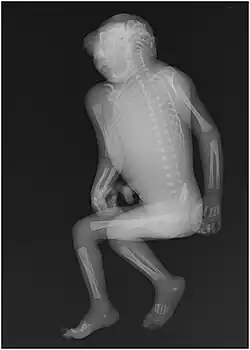

Another health implication is the depletion of folate within the body, where the overexposure to UV light can lead to megaloblastic anemia. Folate deficiency in pregnant women can be detrimental to the health of their newborn babies in the form of neural tube defects, miscarriages, and spina bifida, a birth defect in which the backbone and spinal canal do not close before birth.[104] The peak of neural tube defect occurrences is the highest in the May–June period in the Northern Hemisphere.[2] Folate is needed for DNA replication in dividing cells and deficiency can lead to failures of normal embryogenesis and spermatogenesis.[2][3][55]